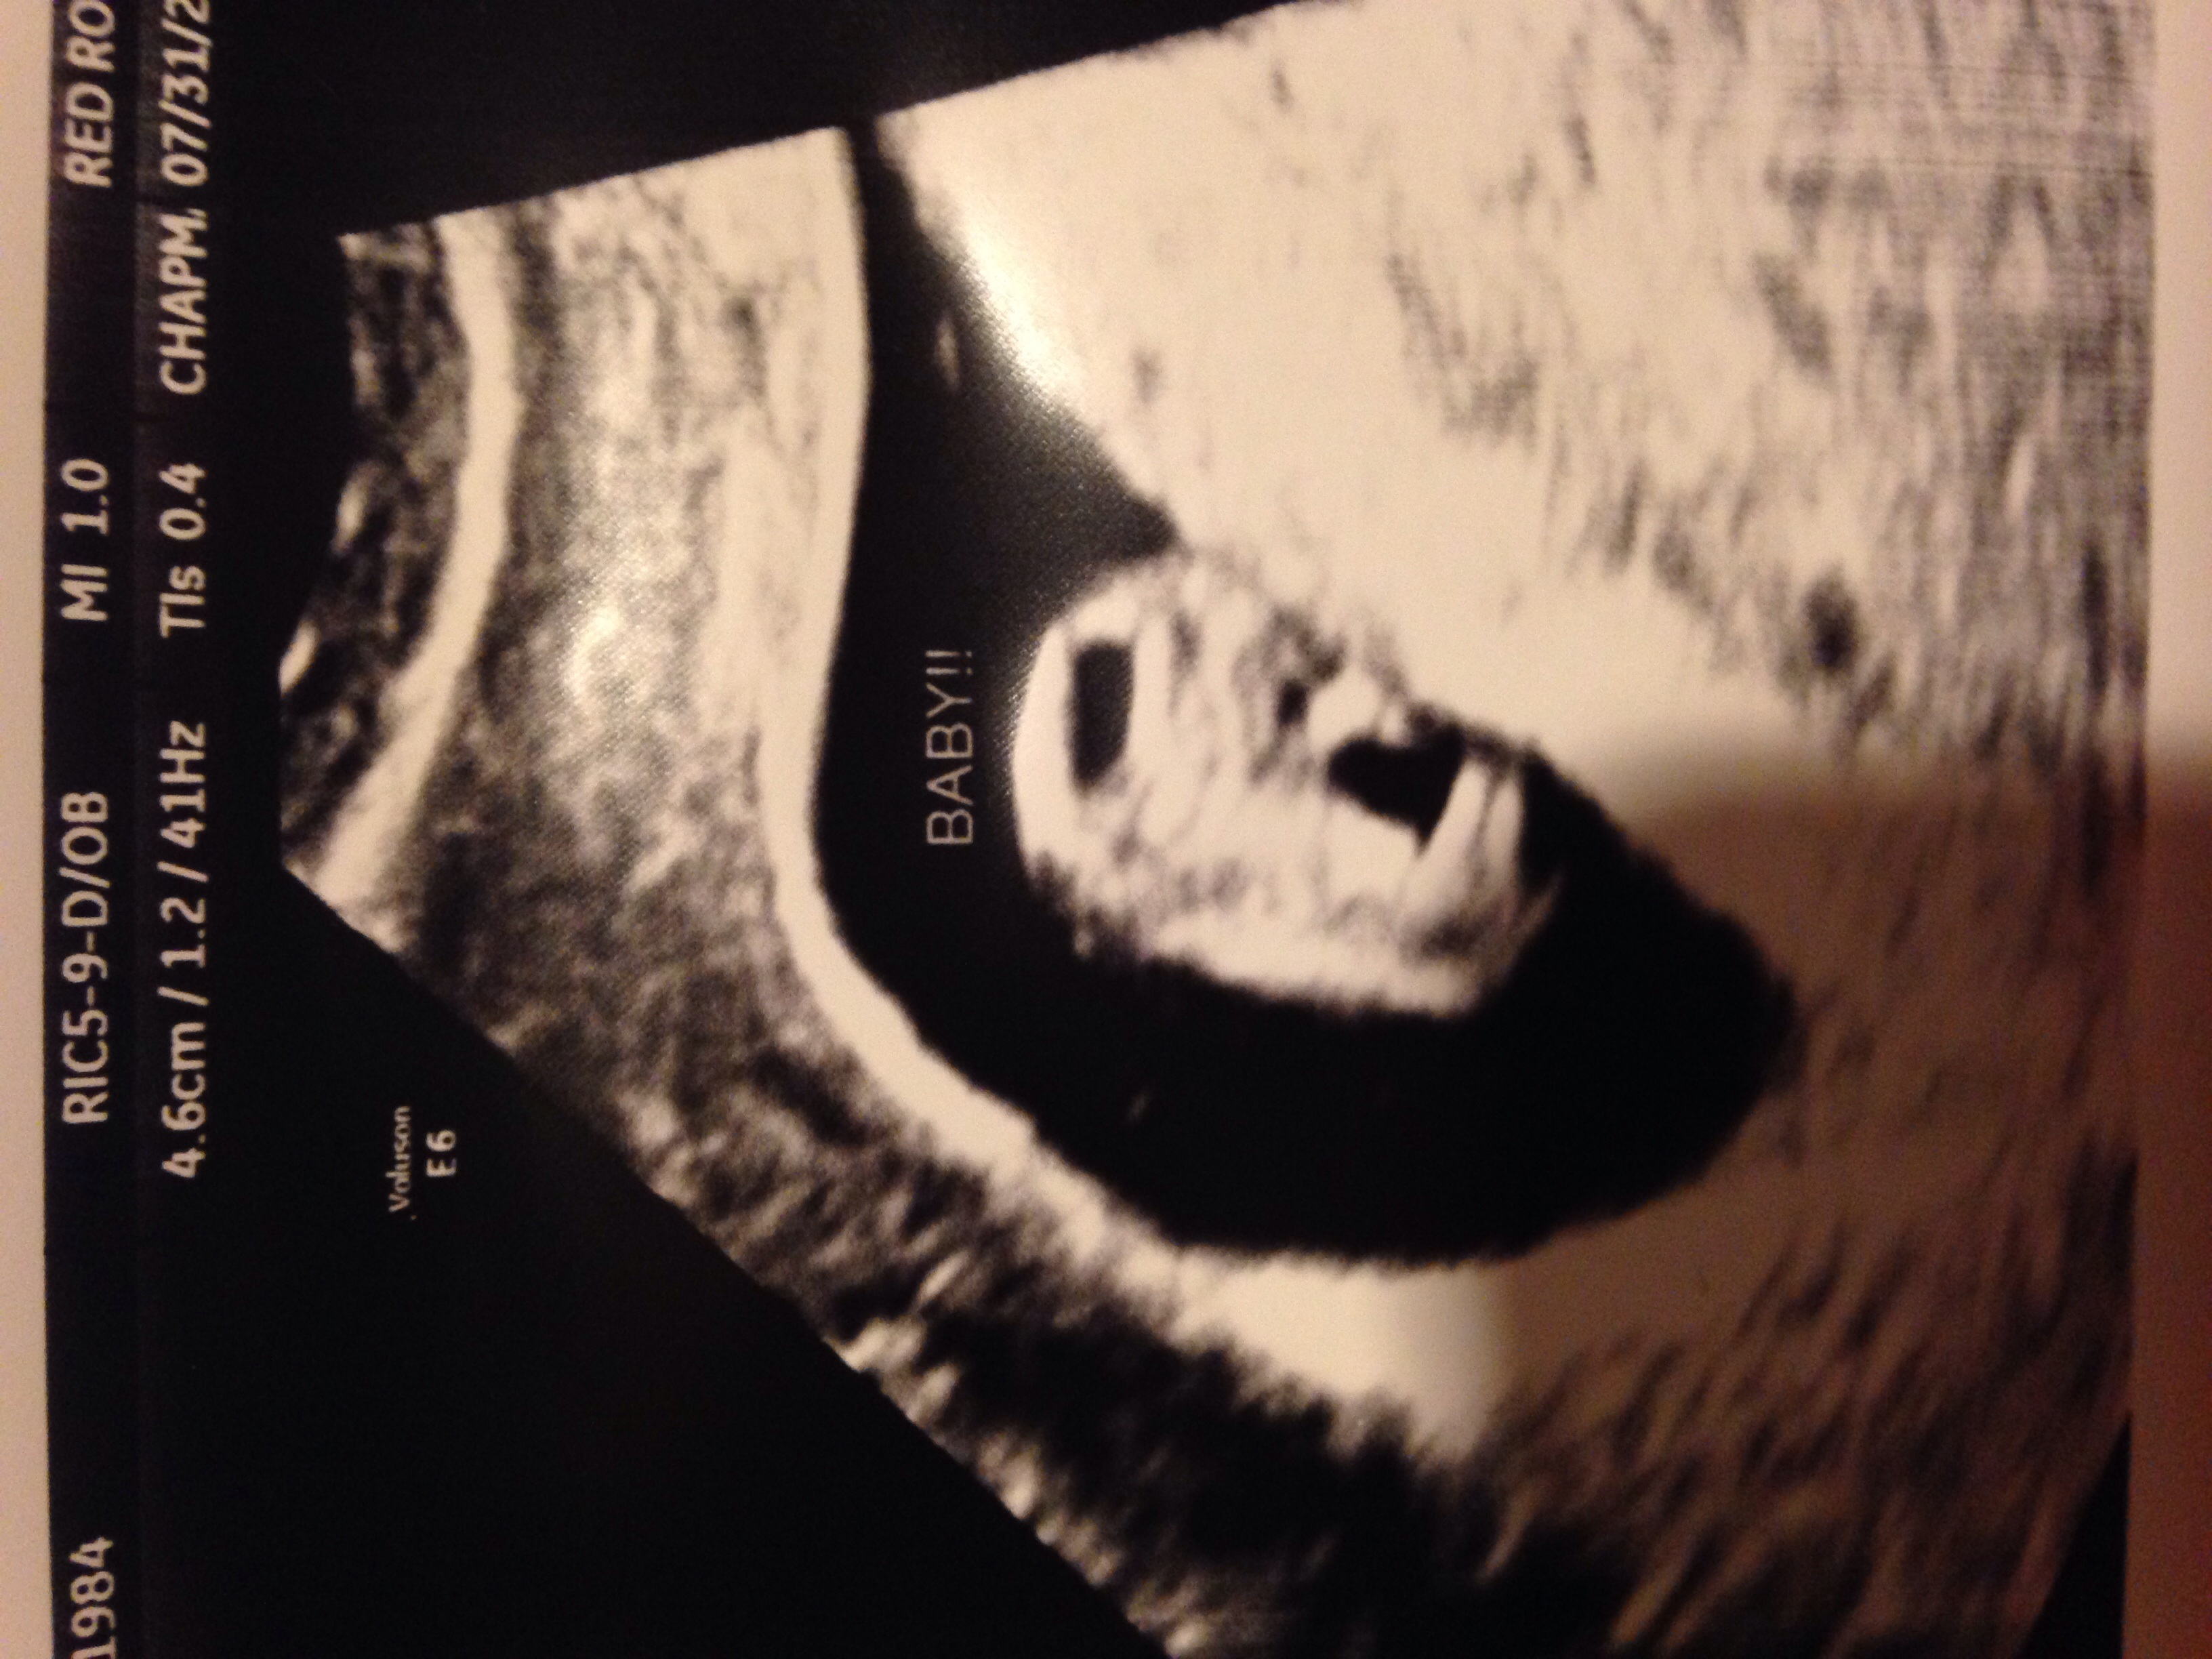

Forgive me in advance if this is a stupid question BUT according to TB at week 8 my baby is the size of a raspberry, measuring a little over a half an inch. Yesterday with my ultrasound, doc says they look for baby to be over 4cm at this phase. Mine was 4.6. If you convert that to inches that's 1.81". Now I'm totally confused... Is it some overgrown steroid SAMs club raspberry TB is referencing or are they different measurements like circumference etc... And like a proud mama already here's my little one!

• Hmm the pic didn't post. Let's try again. The measurement is at the top, plus we had the whole convo about being over 4cm (I remember thinking "phew just made it at 4.6!")

• I haven't had an u/s but I'm thinking the 4.6/1.2/41hz is the ultrasound machine maybe the wand attached. Last I heard, babies didn't have cycles per second (hertz or hz)

• I'm wondering if maybe they meant the whole sack was 4.6 cm? I looked at the picture and the second number after that is 1.2 which would put you more in the range of 8 weeks. I had my 8 week ultrasound on Wednesday and the baby measured in at 1.66 cm which converts correctly to the raspberry size.

• I don't think those numbers are the baby's measurements but something to do with maybe the viewing area. I just looked at my 7w5d ultrasound from yesterday and it says 10.1cm at that place on the top and my baby was def not 10.1cm. However big or small they are, super cute baby you have there! :)